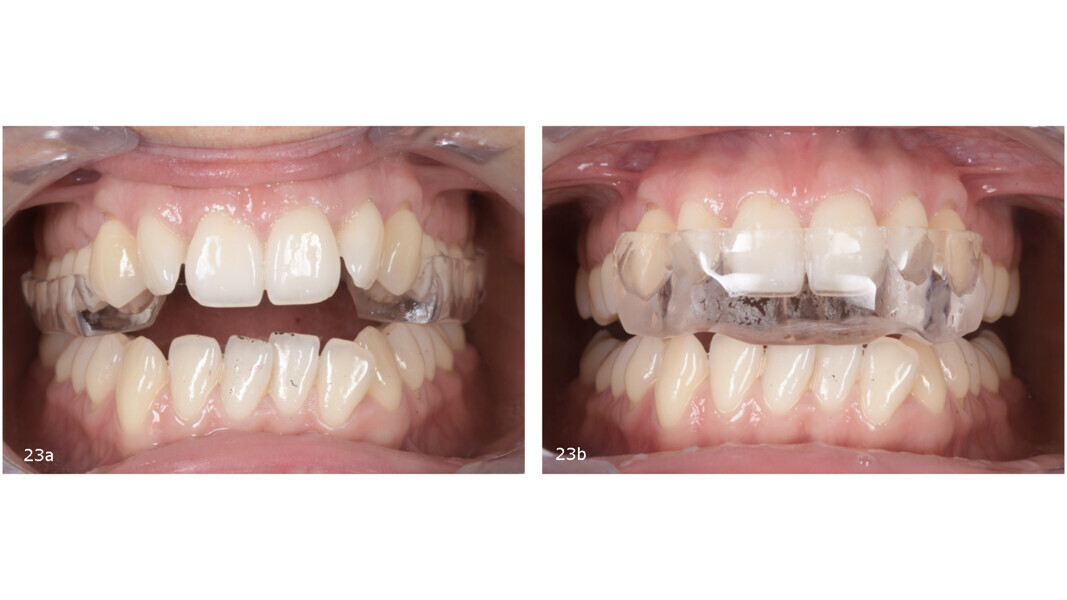

Splint therapy

We selected a two-piece FACE splint, worn 24 hours a day in the posterior segment during the day and the anterior segment at night (Fig. 23). The splint therapy lasted for four months, during which a stable condylar position was achieved, the patient transitioned to a single arc of closure and full remission of TMD symptoms was obtained. As a result of mandibular posterior rotation, the occlusion changed, presenting with an increased anterior open bite (Fig. 24), an increased overjet (Fig. 25) and an increased Class II dental relationship (Fig. 26).